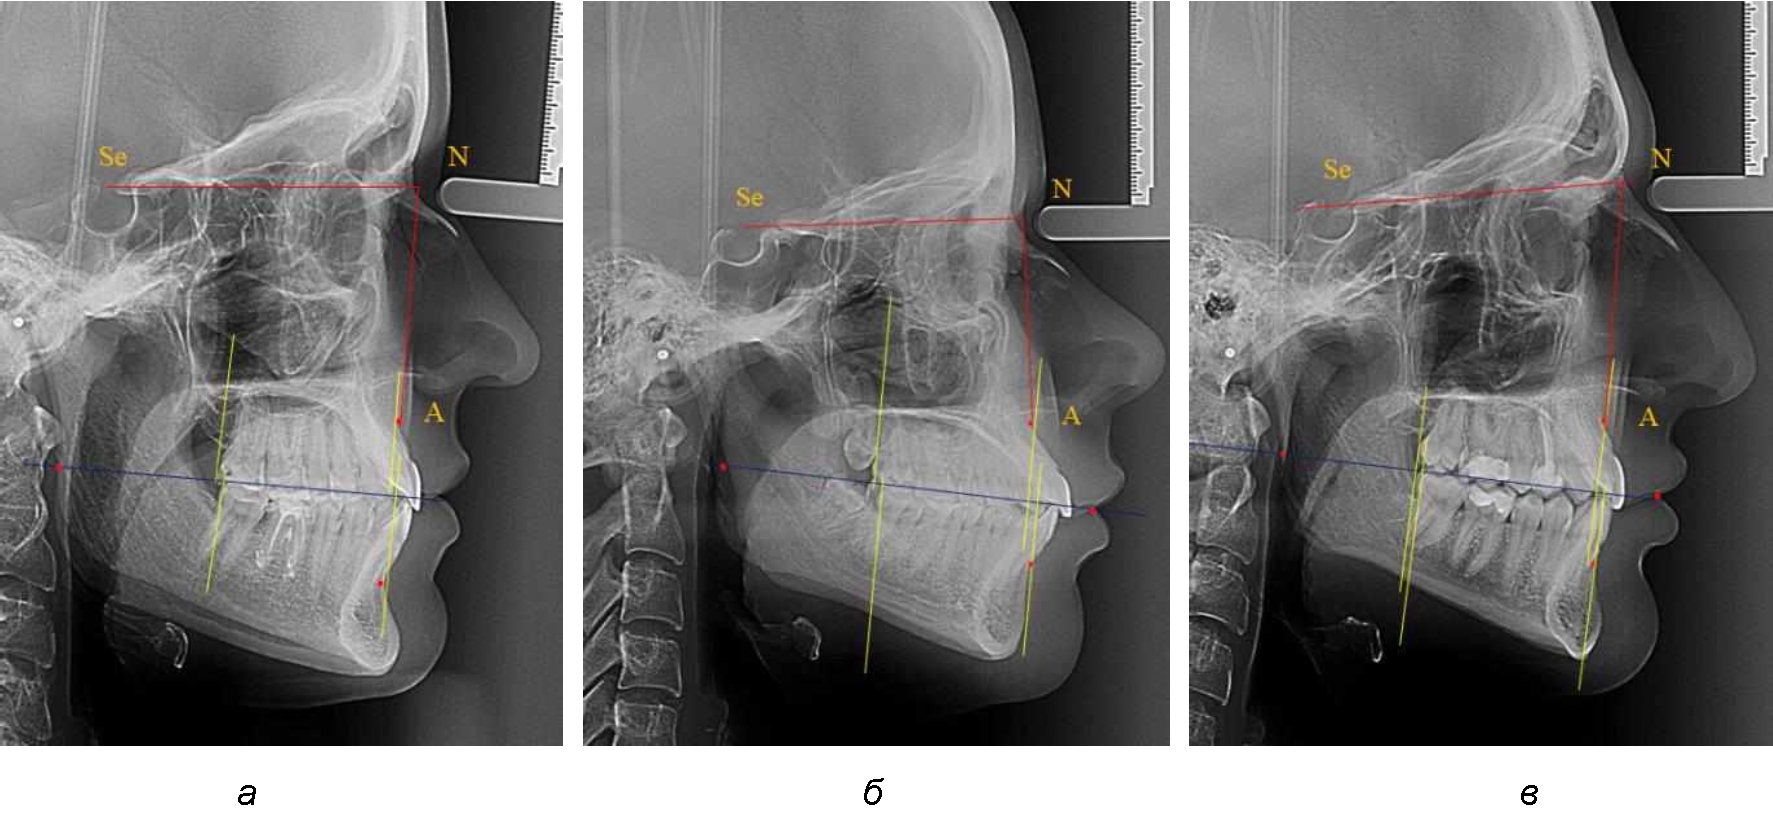

На рентенограммах с признаками дистальной окклюзии Wits-число имело положительные значения. Дистальная точка нижнего моляра была расположена позади верхней дистальной точки окклюзии второго моляра. Относительно равными, так же как и при анализе снимков с мезиальной окклюзией, считались показатели альвеолярно-дентальных размеров, при которых разница не превышала 1,5 мм. Тем не менее расстояние «rmРOcP-A(SS)» превышало расстояние «rmРOcP-B(SM)» в среднем по группе на (5,29 ± 1,47) мм (рис. 4).

Рис. 4. Положение апикальных точек и челюстей при дистальной окклюзии с равными (а) и разными (б) альвеолярно-дентальными размерами зубочелюстных дуг

В тех случаях, когда при дистальной окклюзии альвеолярно-дентальные размеры были различными, размер нижней челюсти превышал аналогичный параметр верхней челюсти, в среднем на (3,62 ± 1,12) мм.

Таким образом, размеры и положения челюстей при физиологической окклюзии, как правило, были практически равны между собой, не зависимо от типологических особенностей зубочелюстных дуг и положения челюстей в структуре лицевого отдела головы. Полученные данные были использованы при анализе размеров и положения челюстей у людей с аномалиями окклюзии в сагиттальном направлении. При этом, было отмечено два основных варианта, как при мезиальной, так и при дистальной окклюзии, а именно с равными и различными размерами челюстей. Данные позволят клиницистам определять тактику проведения лечебных мероприятий.